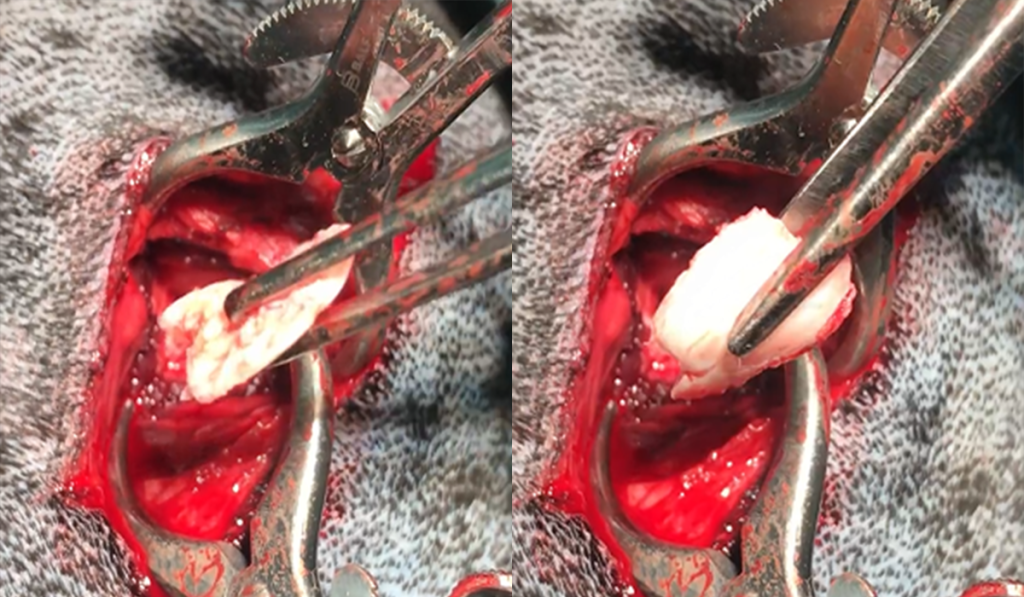

Пример из практики Кардаш М.А.: как выглядит отслоившийся хрящ во время операции.

Артротомия – это процедура, при которой полость сустава раскрывается через небольшой разрез размером 2-4 см. Ее используют при наличии крупных дефектов и глубоких поражений хряща. Артротомия проводится чаще благодаря своей способности обеспечить тщательную санацию сустава и удаление всей патологической ткани, что является важным этапом в восстановлении полноценной функции сустава.